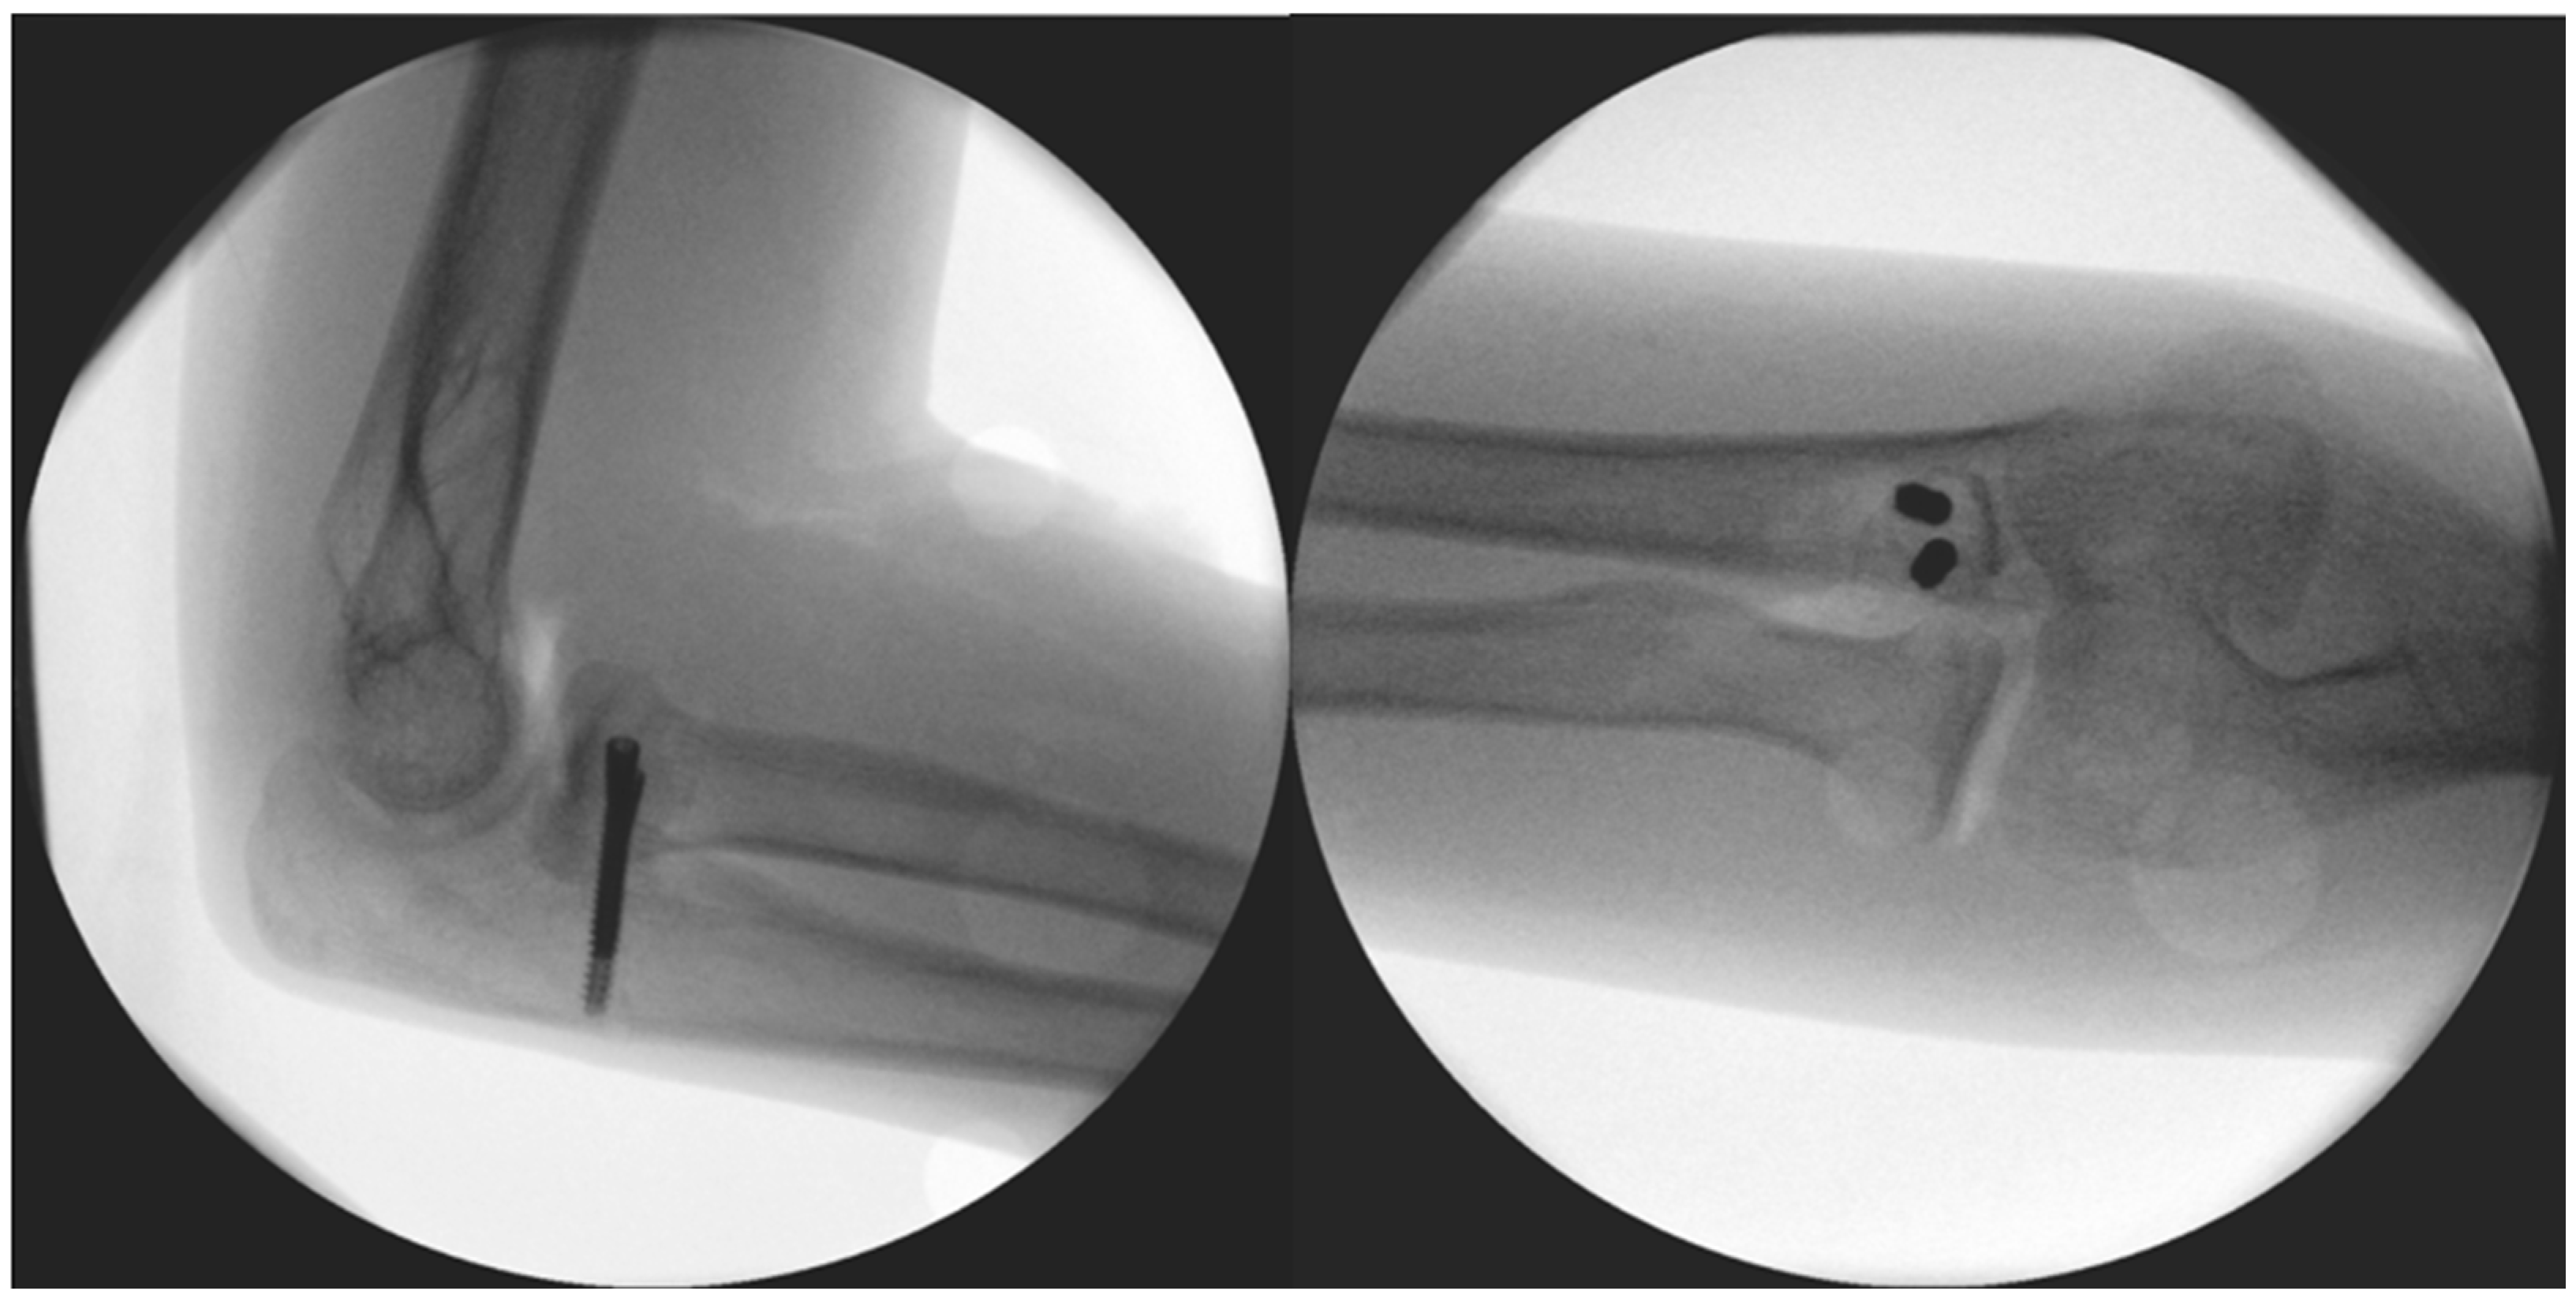

Figure 4.

Immediate post-op images of the fixation.

The surgery took place after disinfection and isolation, under general anesthesia, in exsanguinated conditions, and with prophylactic antibiotic protection (1 g Cefazolin) and took 90 min to complete. We used a ventral longitudinal incision along the anterior aspect of the elbow, following the modified Henry approach. After incising the skin and subcutaneous tissue, the bicipital aponeurosis was identified and carefully incised to expose the underlying brachial artery and median nerve, which were mobilized and retracted medially for protection. The biceps tendon was retracted laterally to enhance visualization. The brachialis muscle was then split longitudinally in line with its fibres, allowing access to the anterior joint capsule. Once the capsule was incised, the pronator teres was identified along its ulnar attachment and gently retracted, providing direct exposure to the coronoid process for reconstruction, facilitating precise debridement and accurate graft placement. The 2 × 1.5 × 3 millimetre (mm) bone fragment was removed. Histological analysis did not identify underlying pathology and proved that the fragment was otherwise formed of healthy bone tissue. The autograft was obtained from the iliac ala. From here, a 1 × 1 × 1 centimetre (cm) corticospongious piece was borrowed and reattached to the refreshed spongious surface of the coronoid process with two, one 26 and one 28 mm in length, A-spire (Sanatmetal Ltd., Eger, Hungary) screws (Figure 4). The graft size was determined based on the intraoperatively measured defect and used to restore anatomical height and contour to ensure joint congruity and stability. The recipient site was refreshed to gain access to a fresh vascular supply for graft incorporation with the help of a Volkmann spoon. A drain was applied, and after the reconstruction of the superficial layers, the skin was sutured. No additional reconstruction or reinforcement was needed for the median collateral ligament (MCL), as both the anterior and posterior maintained proper ligamentous integrity during the stability test. After swathing and bandaging, a 90° cast was applied, which was utilized for one month.